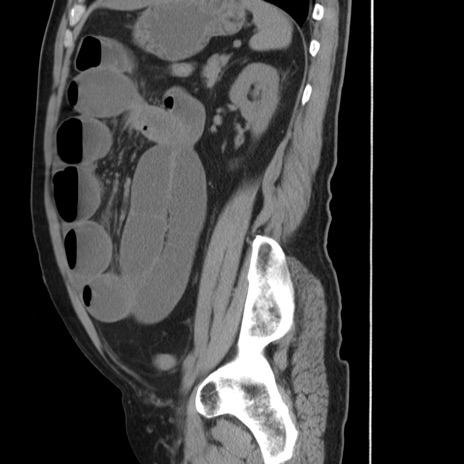

症例20(矢状断像)

【症例】 60歳代男性

【主訴】 腹部膨満、嘔吐

【現病歴】5日前頃より倦怠感を認め食事量減少し4日前の朝嘔吐、食事摂取困難となった。 3日前近医受診し点滴施行され整腸剤などを処方された。 当日他院を受診し、腹部膨満著明、炎症反応の上昇(CRP10.8、WBC11200)あり、紹介受診となる。

【身体所見】 意識JCS1 受け答えがはっきりしないBP 111/57mHg、 P 67bpm、、BT35.2°C、SpO2 97%(RA)、 腹部:膨隆、打診で鼓音あり、全体的に圧痛有り、腸蠕動音(-)、反跳痛ははっきりせず。

【データ】WBC 11400、CRP 14.20